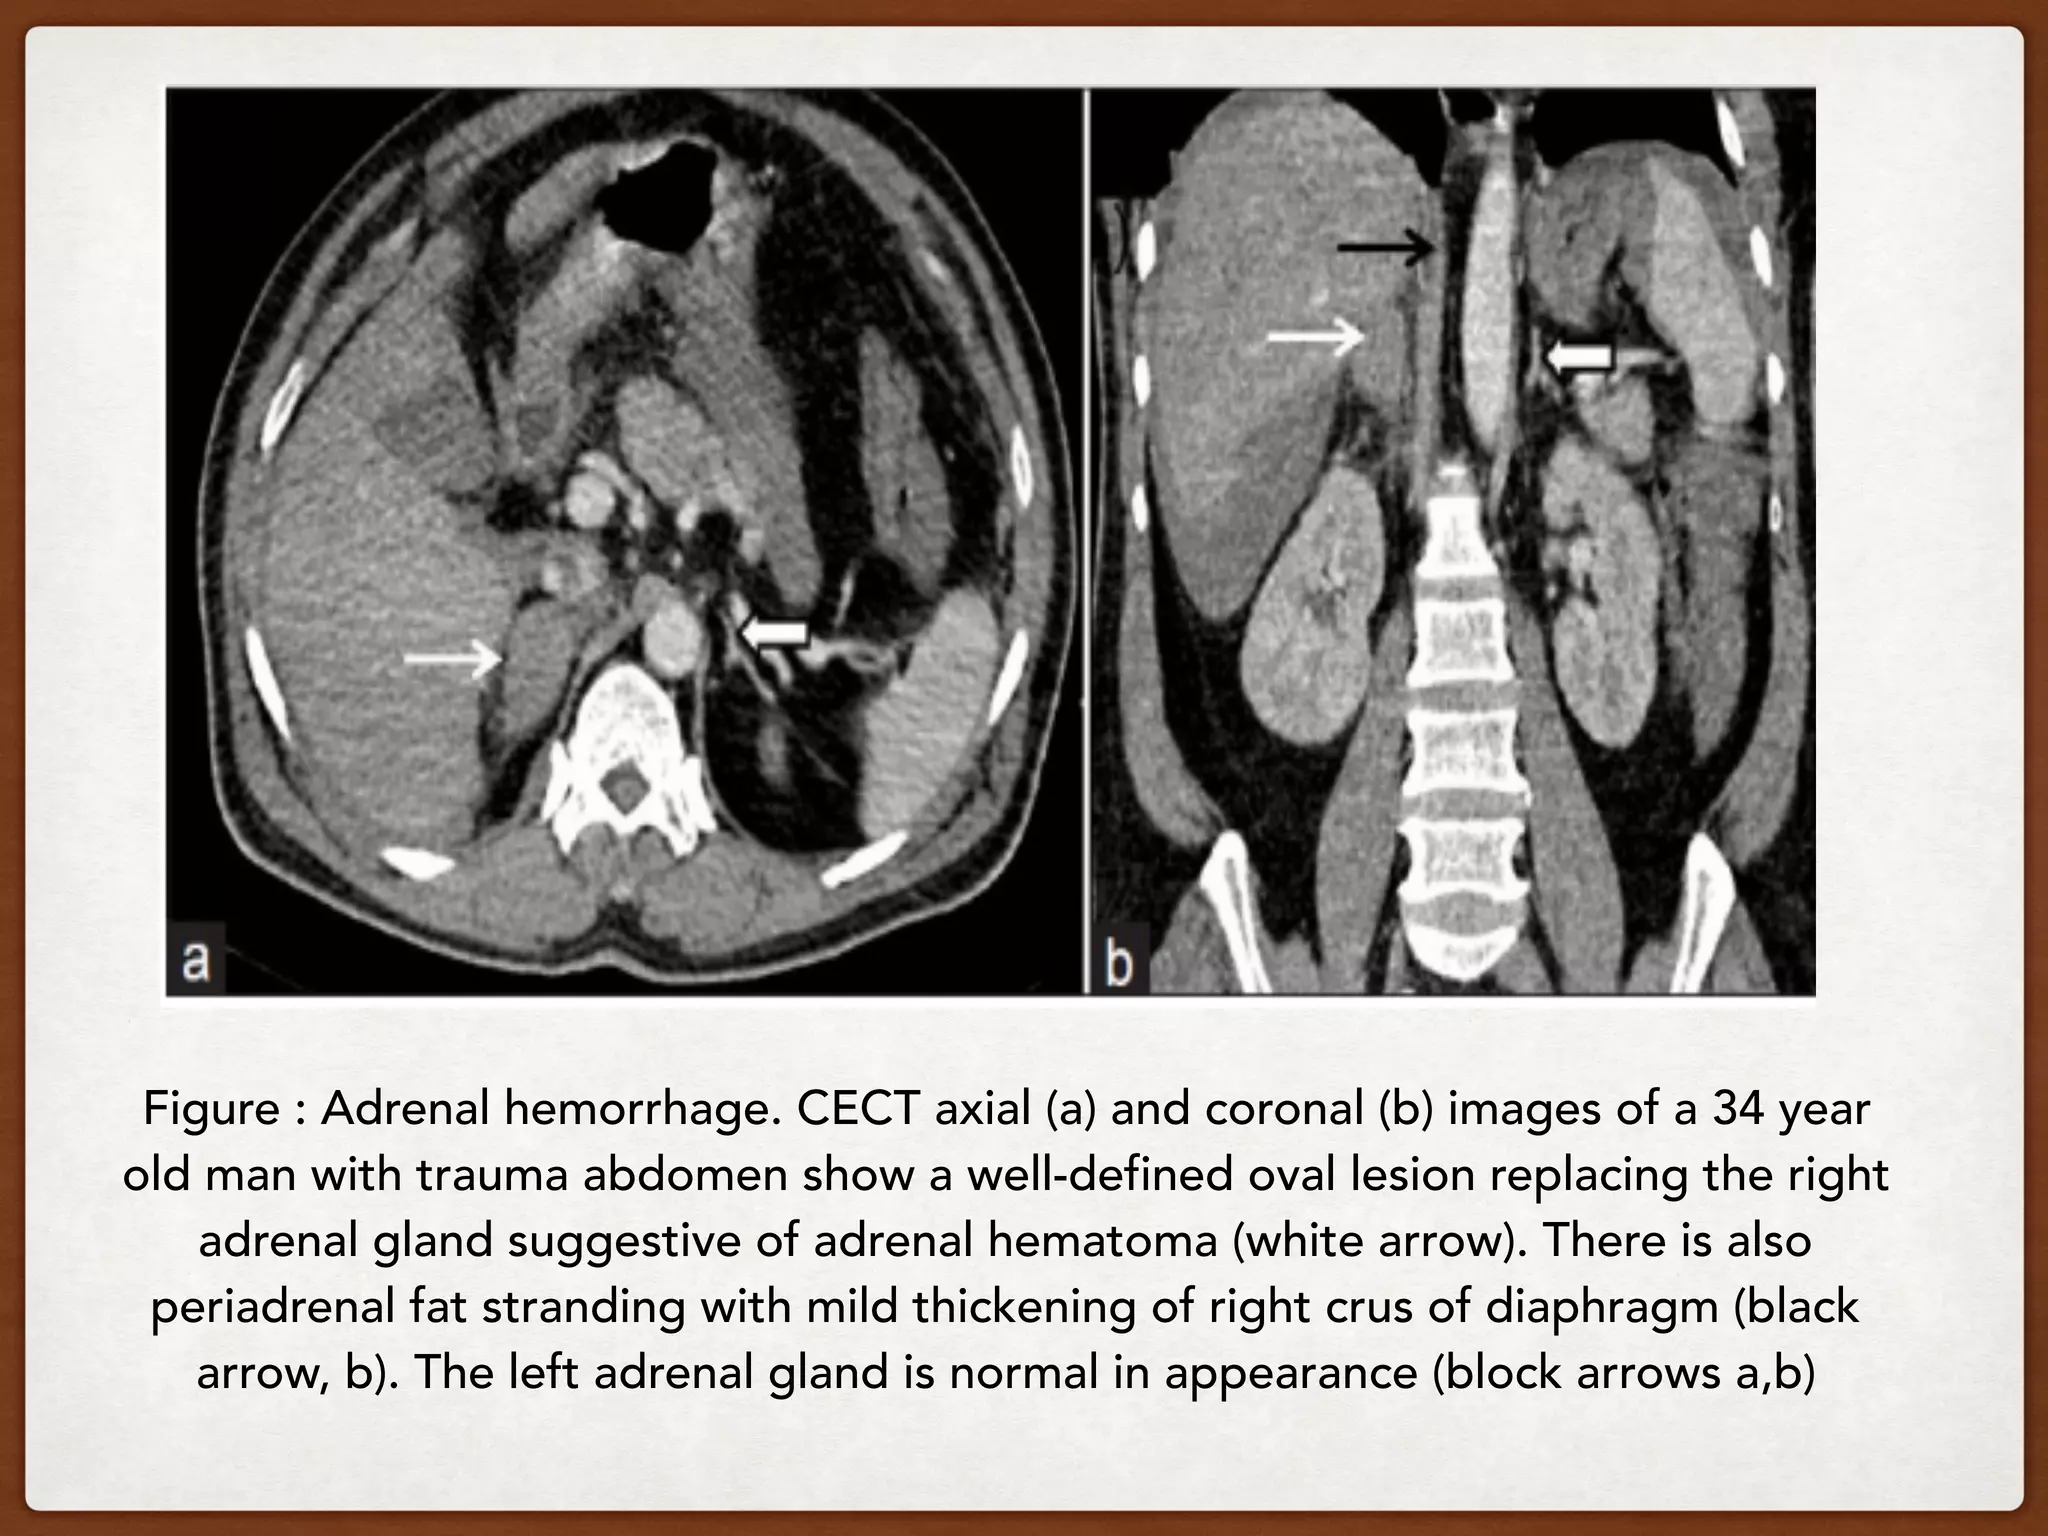

Adrenal hemorrhage

Adrenal hemorrhage is usually encountered in

patients with blunt abdominal trauma where it affects

right adrenal more than the left.

Non-traumatic adrenal hemorrhage occurs rarely and is

associated with stress, hemorrhagic diathesis,

coagulopathy or anticoagulation therapy and in the

case of underlying adrenal tumors.

On unenhanced CT, hemorrhage demonstrates

attenuation values of 50-90 HU in acute and

subacute stage with a gradual decrease in size

and attenuation on follow-up imaging.

Does not enhance, decreases in size and

attenuation with time. Fat stranding & extension

is common.

Figure : Adrenal hemorrhage. CECT axial (a) and coronal (b) images of a 34 year

old man with trauma abdomen show a well-defined oval lesion replacing the right

adrenal gland suggestive of adrenal hematoma (white arrow). There is also

periadrenal fat stranding with mild thickening of right crus of diaphragm (black

arrow, b). The left adrenal gland is normal in appearance (block arrows a,b)